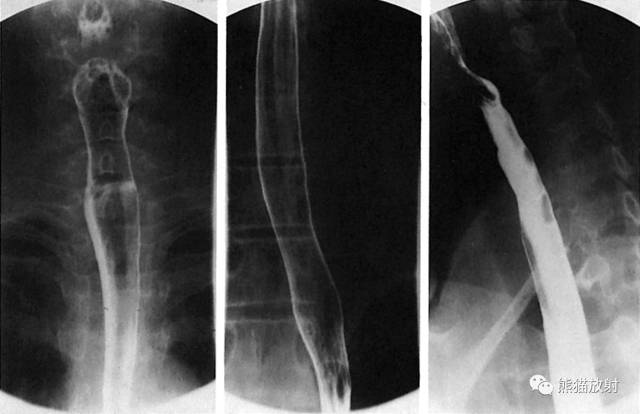

3 Esophagus 食管

1 Uvula 悬雍垂,2 Lateral glossoepiglottic fold 舌会厌外侧襞,3 Epiglottis 会厌,4 Piriform recess 梨状隐窝,5 Upper esophageal sphincter 食管上括约肌,6 Body of the esophagus 食管体部,7 Aortic arch 主动脉弓,8 Bronchial and aortic segment 支气管及主动脉段,A Paratracheal segment 气管旁段,B Aortic segment 主动脉段,C Bronchial segment 支气管段,D Interbronchial segment 支气管间段,E Retrocardiac segment 心后段,F Epiphrenic segment 膈上段